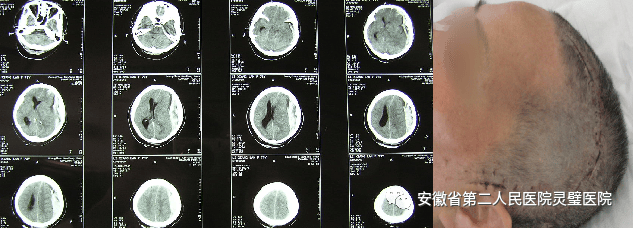

一、颅脑创伤个体化精准救治技术

颅脑创伤是神经外科常见病、多发病,近十年来,我们成功诊治了大量重型颅脑损伤患者,尤其在特重型颅脑损伤、原发性脑干伤、弥漫性轴索损伤等方面积累了丰富的经验,并形成了以“神经多模态监测、亚低温治疗、镇静镇痛、大骨瓣减压以及精准化脑保护”等核心技术为特色的一体化标准化救治方案,重型颅脑创伤患者死亡率逐年降低,达到国内一流水平。

硬膜下血肿、脑挫裂伤术前和术后 颅内压监测

大骨瓣减压术治疗硬膜下血肿及切口

后颅窝及小脑半球外伤手术前后

重型颅脑损伤(GCS 3分),脑疝,个体化切口设计